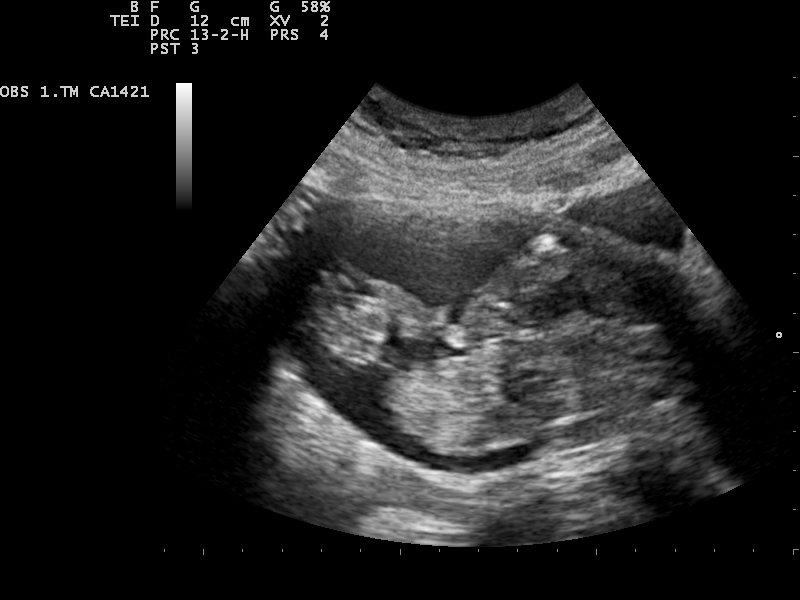

L'ecografia morfologica si esegue tra le 19 e le 21 settimane ed è una delle ecografie più importanti di tutta la gravidanza, poiché è quella in cui viene analizzata con più accuratezza l'anatomia del feto Consente infatti di esaminare tutti gli organi del feto, dalla testa ai piedi.

Ecografia morfologica. L’ecografia morfologica, che solitamente viene effettuata tra la ventesima e la ventitreesima settimana di gravidanza, permette l’analisi morfologica del feto valutando i rapporti tra le dimensioni del feto e la quantità di liquido amniotico È questa senza dubbio l’ecografia più importante di tutta la gravidanza. L’ecografia morfologica viene eseguita dalla ventesima alla ventitreesima settimana di gestazione ed è, assieme all’ecografia del primo trimestre, il controllo più importante e complesso di tutta la gravidanza Questa ecografia viene detta morfologica appunto perché è destinata a studiare la morfologia del feto per escludere, o accertare, la presenza di malformazioni. L’ecografia morfologica prevede la valutazione delle dimensioni del feto (biometria fetale), dell’impianto e della struttura della placenta, della quantità di liquido amniotico, del collo dell’utero, ma fornisce soprattutto uno studio analitico di tutti i distretti anatomici esplorabili nel feto.

L’ecografia morfologica costituisce attualmente parte integrante della diagnosi prenatale non invasiva Poiché tale valutazione viene effettuata a 1922 settimane gestazionali, l’ecografia morfologica non costituisce un metodo di screening elettivo per la valutazione di un aumento del rischio per anomalie cromosomiche o genetiche. Che cos’è l’ecografia morfologica?. Ecografia delle 1922 settimane la morfologica L’approccio all’ecografia morfologica è sistematico, cioè si guardano gli organi in una sequenza ben definita Si parte solitamente dall’alto, descrivendo testa, torace, addome, colonna, arti.

L’ecografia morfologica prevede la valutazione delle dimensioni del feto (biometria fetale), dell’impianto e della struttura della placenta, della quantità di liquido amniotico, del collo dell’utero, ma fornisce soprattutto uno studio analitico di tutti i distretti anatomici esplorabili nel feto. Ecografia delle 1922 settimane la morfologica L’approccio all’ecografia morfologica è sistematico, cioè si guardano gli organi in una sequenza ben definita Si parte solitamente dall’alto, descrivendo testa, torace, addome, colonna, arti. En el ultimo tiempo a la ecografia de las 2224 semanas "morfologica" clasica que va por el abdomen se le ha agregado una parte transvaginal para medir la longitud de tu cuello uterino Se hace como screening de parto prematuro (si esta corto, hay mas riesgo).